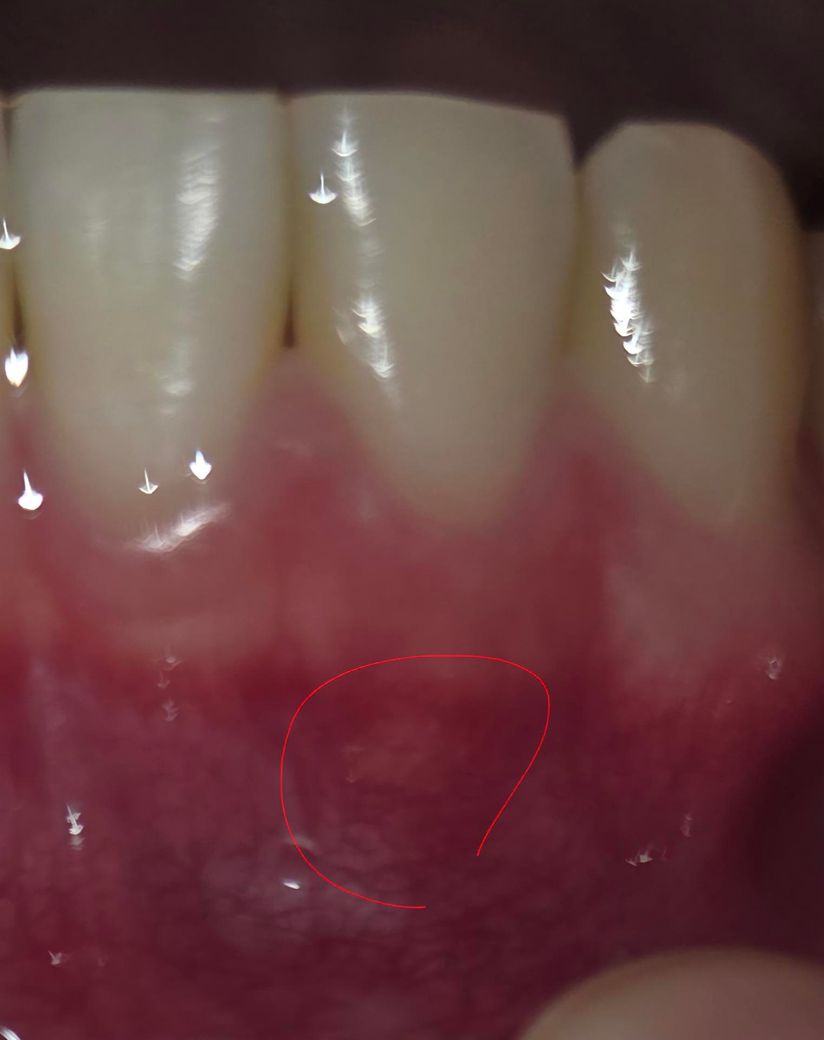

이거 치아 뿌리 염증인가요? 많은 의사분들의 답변 부탁드립니다.

아침에 일어나니 구내염이 특이한 곳에 생겼다 싶었는데 동그라민 친 부분 잇몸 바로 아래쪽이네요. 통증은 누르거나 압박을 가하면 있고요. 해당 동그라미 친 위쪽 아랫니 치아는 씹어서 압박을 가해도 통증은 없습니다. 만약 뿌리 염증이라면 치과를 가야 할 것 같은데 뿌리 아래쪽이라 그냥 구내염인가요? 아니면 뿌리 염증도 저렇게 잇몸 아랫쪽에서 시작하나요?

사진상으로는 치아 뿌리 염증은 아닌거 같습니다. 구내염일 가능성이 더 높아 보이니 치과에 가셔서 검진을 받아보세요.

뿌리염증보다는 구내염일 가능성이 높지만 치아에 통증이 느껴진다면 치과 가보셔야 합니다.

사진으로 봤을 경우 염증이 보이거나 하진 않습니다. 측은한 부위에 염증을 확인하기 위해서는 방사선 사진 등이 필요할 수 있습니다.

자세한 확인을 위해서 치과에서 진료를 받아보는 것을 권유드립니다.

사진의 양상을 봤을때는 구내염 맞을 것 같습니다 자극적인 음식 피하시고, 오라메디 연고 바르시면 좋습니다